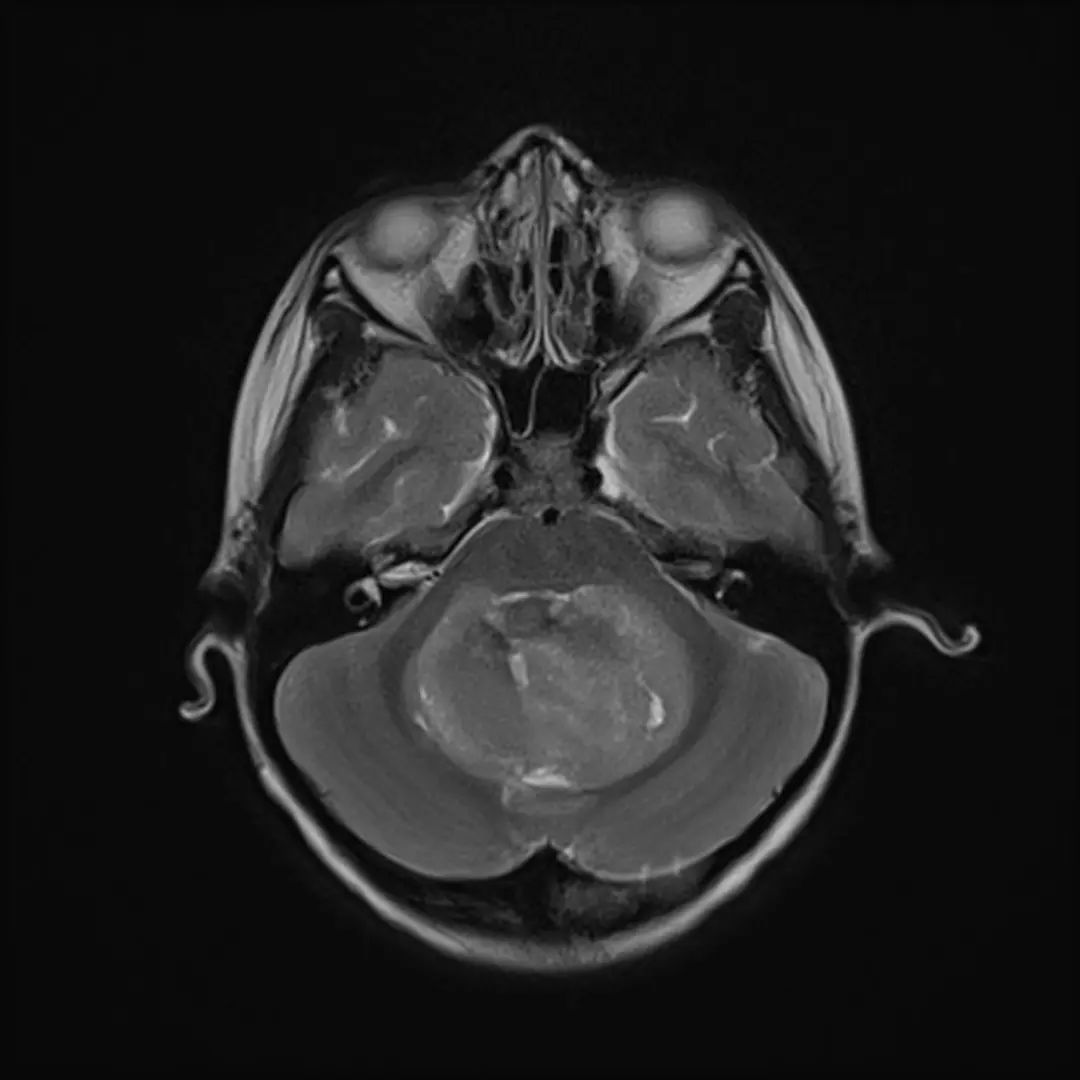

MRI表现

- T1WI:等/略低信号,T2WI上呈等/高信号。

- 边界:清晰,瘤周轻度水肿。

- 增强后:均匀强化,典型“小囊大结节”征象。

- 成人表现:MRI与CT表现均不典型。

中线小脑肿块,充满第四脑室并压迫脑干和小脑。与周围正常小脑相比,肿瘤在T1 WI上呈低信号,在T2 WI上呈轻度高信号,不均匀强化,呈囊/坏死成分,弥散受限。病理髓母细胞瘤。